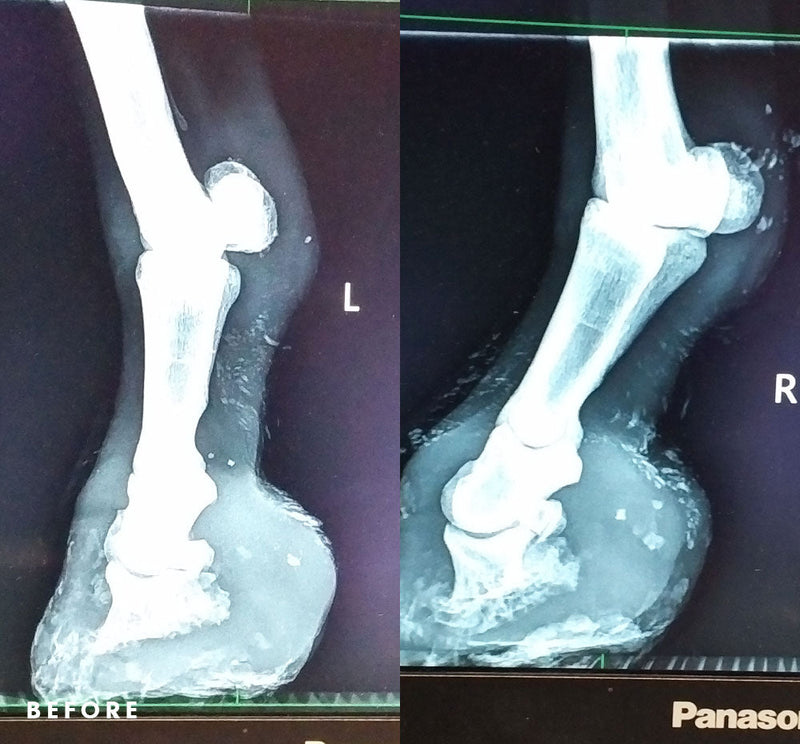

Sweet Granny Finds Relief Our 20-something-year-old donkey, Granny, is elderly, but age isn’t what’s troubling her. Granny has severe arthritis and laminitis in her hooves...